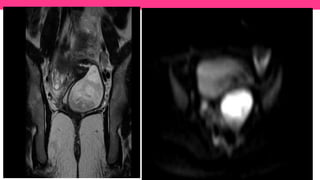

• #36 A) Axial and (B) Coronal T2 WI shows párt of the left hemi-uterus (long arrow) and left hemi-vagina distended (short arrow) with hypointense fluid representing blood products